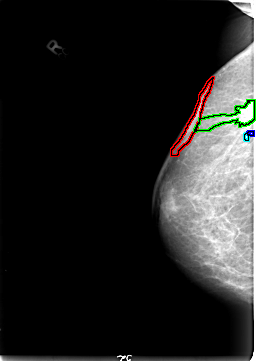

B_3025_1.RIGHT_MLO

FILE: B_3025_1.RIGHT_MLO.OVERLAY

TOTAL_ABNORMALITIES 4

ABNORMALITY 1

LESION_TYPE MASS SHAPE IRREGULAR-ARCHITECTURAL_DISTORTION MARGINS ILL_DEFINED-SPICULATED

ASSESSMENT 5

SUBTLETY 5

PATHOLOGY MALIGNANT

ABNORMALITY 2

LESION_TYPE CALCIFICATION TYPE PLEOMORPHIC-FINE_LINEAR_BRANCHING DISTRIBUTION SEGMENTAL

ABNORMALITY 3

ABNORMALITY 4